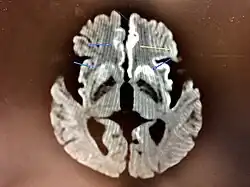

Magnetic resonance image of sporadic CJD[2]

Through the image of MRI, the obvious precipitation of prion protein in the brain is visible.

Spongiform change in CJD

The classic histologic appearance is spongiform change in the gray matter: the presence of many round vacuoles from one to 50 micrometers in the neuropil, in all six cortical layers in the cerebral cortex, or with diffuse involvement of the cerebellar molecular layer.[59] These vacuoles appear glassy or eosinophilic and may coalesce. Neuronal loss and gliosis are also seen.[60] Plaques of amyloid-like material can be seen in the neocortex in some cases of CJD.[61]

However, extra-neuronal vacuolization can also be seen in other disease states. Diffuse cortical vacuolization occurs in Alzheimer's disease, and superficial cortical vacuolization occurs in ischemia and frontotemporal dementia. These vacuoles appear clear and punched out. Larger vacuoles encircling neurons, vessels, and glia are a possible processing artifact.[58]